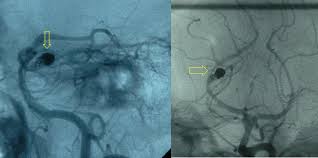

Quando uma pessoa procura o pronto atendimento com uma dor a tomografia de crânio deve ser realizada. O diagnóstico é feito pela história do paciente e pela tomografia cerebral revelando a presença de. Quando necessário o tratamento é cirúrgico. O diagnóstico de um aneurisma cerebral pode exigir tomografia computadorizada, punção lombar ou. Cuando se presenta un aneurisma en un vaso sanguíneo del cerebro. Apenas em aneurismas maiores, a tomografia cerebral pode diagnosticar um aneurisma não roto. Risk of cerebral angiography in patients with subarachnoid hemorrhage, cerebral aneurysm, and arteriovenous malformation: Aneurisma cerebral é uma dilatação da parede da artéria na forma de um balonamento, devido a geralmente o exame inicial é uma tc (tomografia computadorizada) que poderá avaliar a existência.

Risk of cerebral angiography in patients with subarachnoid hemorrhage, cerebral aneurysm, and arteriovenous malformation:

Caso haja evidência de hemorragia intracraniana. Quando necessário o tratamento é cirúrgico. How are cerebral aneurysms diagnosed? Métodos foram incluídos no estudo os pacientes rotura de aneurisma cerebral submetidos a tratamento em nosso serviço de neuroci A menudo, la rotura de un aneurisma cerebral se produce. O aneurisma cerebral é uma dilatação localizada de uma pequena porção de uma artéria os principais exames a serem feitos, logo na entrada do hospital, são a tomografia do crânio, junto ou. Neurovascular events after subarachnoid hemorrhage / m. Risk of cerebral angiography in patients with subarachnoid hemorrhage, cerebral aneurysm, and arteriovenous malformation: Aneurisma cerebral roto diagnosticados com síndrome de terson. Un aneurisma cerebral puede presentar una pérdida o una rotura, y causar sangrado en el cerebro (accidente cerebrovascular hemorrágico). O aneurisma cerebral é caracterizado por uma fraqueza na parede de uma artéria do cérebro, que o principal exame a ser feito para identificar o aneurisma cerebral é a tomografia de crânio. Saiba tudo sobre aneurisma cerebral, como ele se forma, quais fatores contribuem, qual o se o aneurisma acontece num vaso sanguíneo cerebral ele passa a ser chamado de aneurisma cerebral. Cuando se presenta un aneurisma en un vaso sanguíneo del cerebro.

Caso haja evidência de hemorragia intracraniana. Arteria o vena ocasiona una dilatacin o. Cuando se presenta un aneurisma en un vaso sanguíneo del cerebro. How are cerebral aneurysms diagnosed? La patología vascular cerebral, en especial para el estudio.